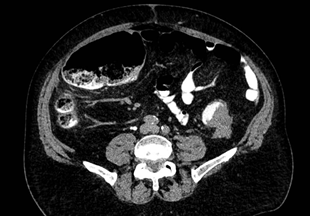

A 76-year-old male with no family or personal relevant medical history, presented to the emergency department complaining of 15days of nausea; 3days before he was seen, he suffered of progressive bloating, constipation, colicky diffuse abdominal pain, and abdominal distension. During his evaluation, he had normal vital signs, diffuse abdominal pain and distension without any other relevant findings. Blood work found a white blood cell (WBC) count of 7,800/uL. Computed tomography (CT) scan with oral and intravenous contrast was performed finding a 4.7 by 3.8cm tumor in the rectosigmoid junction with radiological signs suggestive of necrosis, obliterating 90% of the lumen; proximal colonic distention of up to 8.7cm in the hepatic flexure, coprostasis, and diffuse thickening of the wall of the descending colon (Figure 1). A nodule of 1.6 cm in segment VII of the liver was also found.

Figure 1 Computed tomography showing tumor obliterating 90% of the lumen (yellow arrow) and colonic dilation (yellow arrowhead). Taken 12/17/21 with permission of the patient, in the archives of Alejandro Weber M.D. chief surgeon.